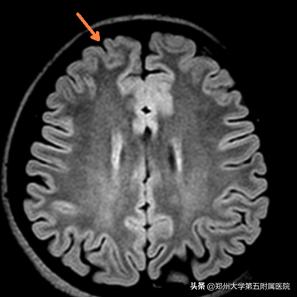

术前影像学评估(头颅MRI提示:考虑左侧额叶白质区点状缺血灶,但细看右额极似有脑发育不良,PET-CT提示右